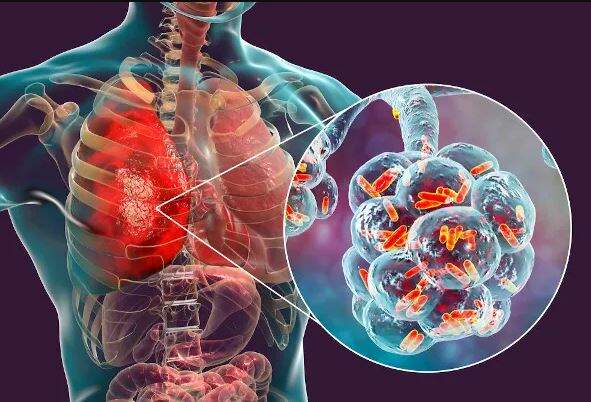

“Seria uma viagem de 30 horas, longa e cansativa. Ele não é um paciente qualquer, precisamos ter esse cuidado”, completou Kalil sobre a viagem do chefe do Executivo à China. Lula foi diagnosticado com “broncopneumonia bacteriana e viral por influenza A” e está em tratamento com uso de antibióticos desde a noite de quinta (23).

Lula tem 77 anos e passou por uma bateria de exames em Brasília em fevereiro. Em novembro do ano passado, chegou a ser internado no Hospital Sírio-Libanês, em São Paulo, para realizar um procedimento de laringoscopia e retirada de uma leucoplasia na prega vocal esquerda, que é uma alteração na mucosa da garganta.

O presidente teve um câncer na laringe, em 2011, e encerrou o tratamento contra a doença em fevereiro de 2012.